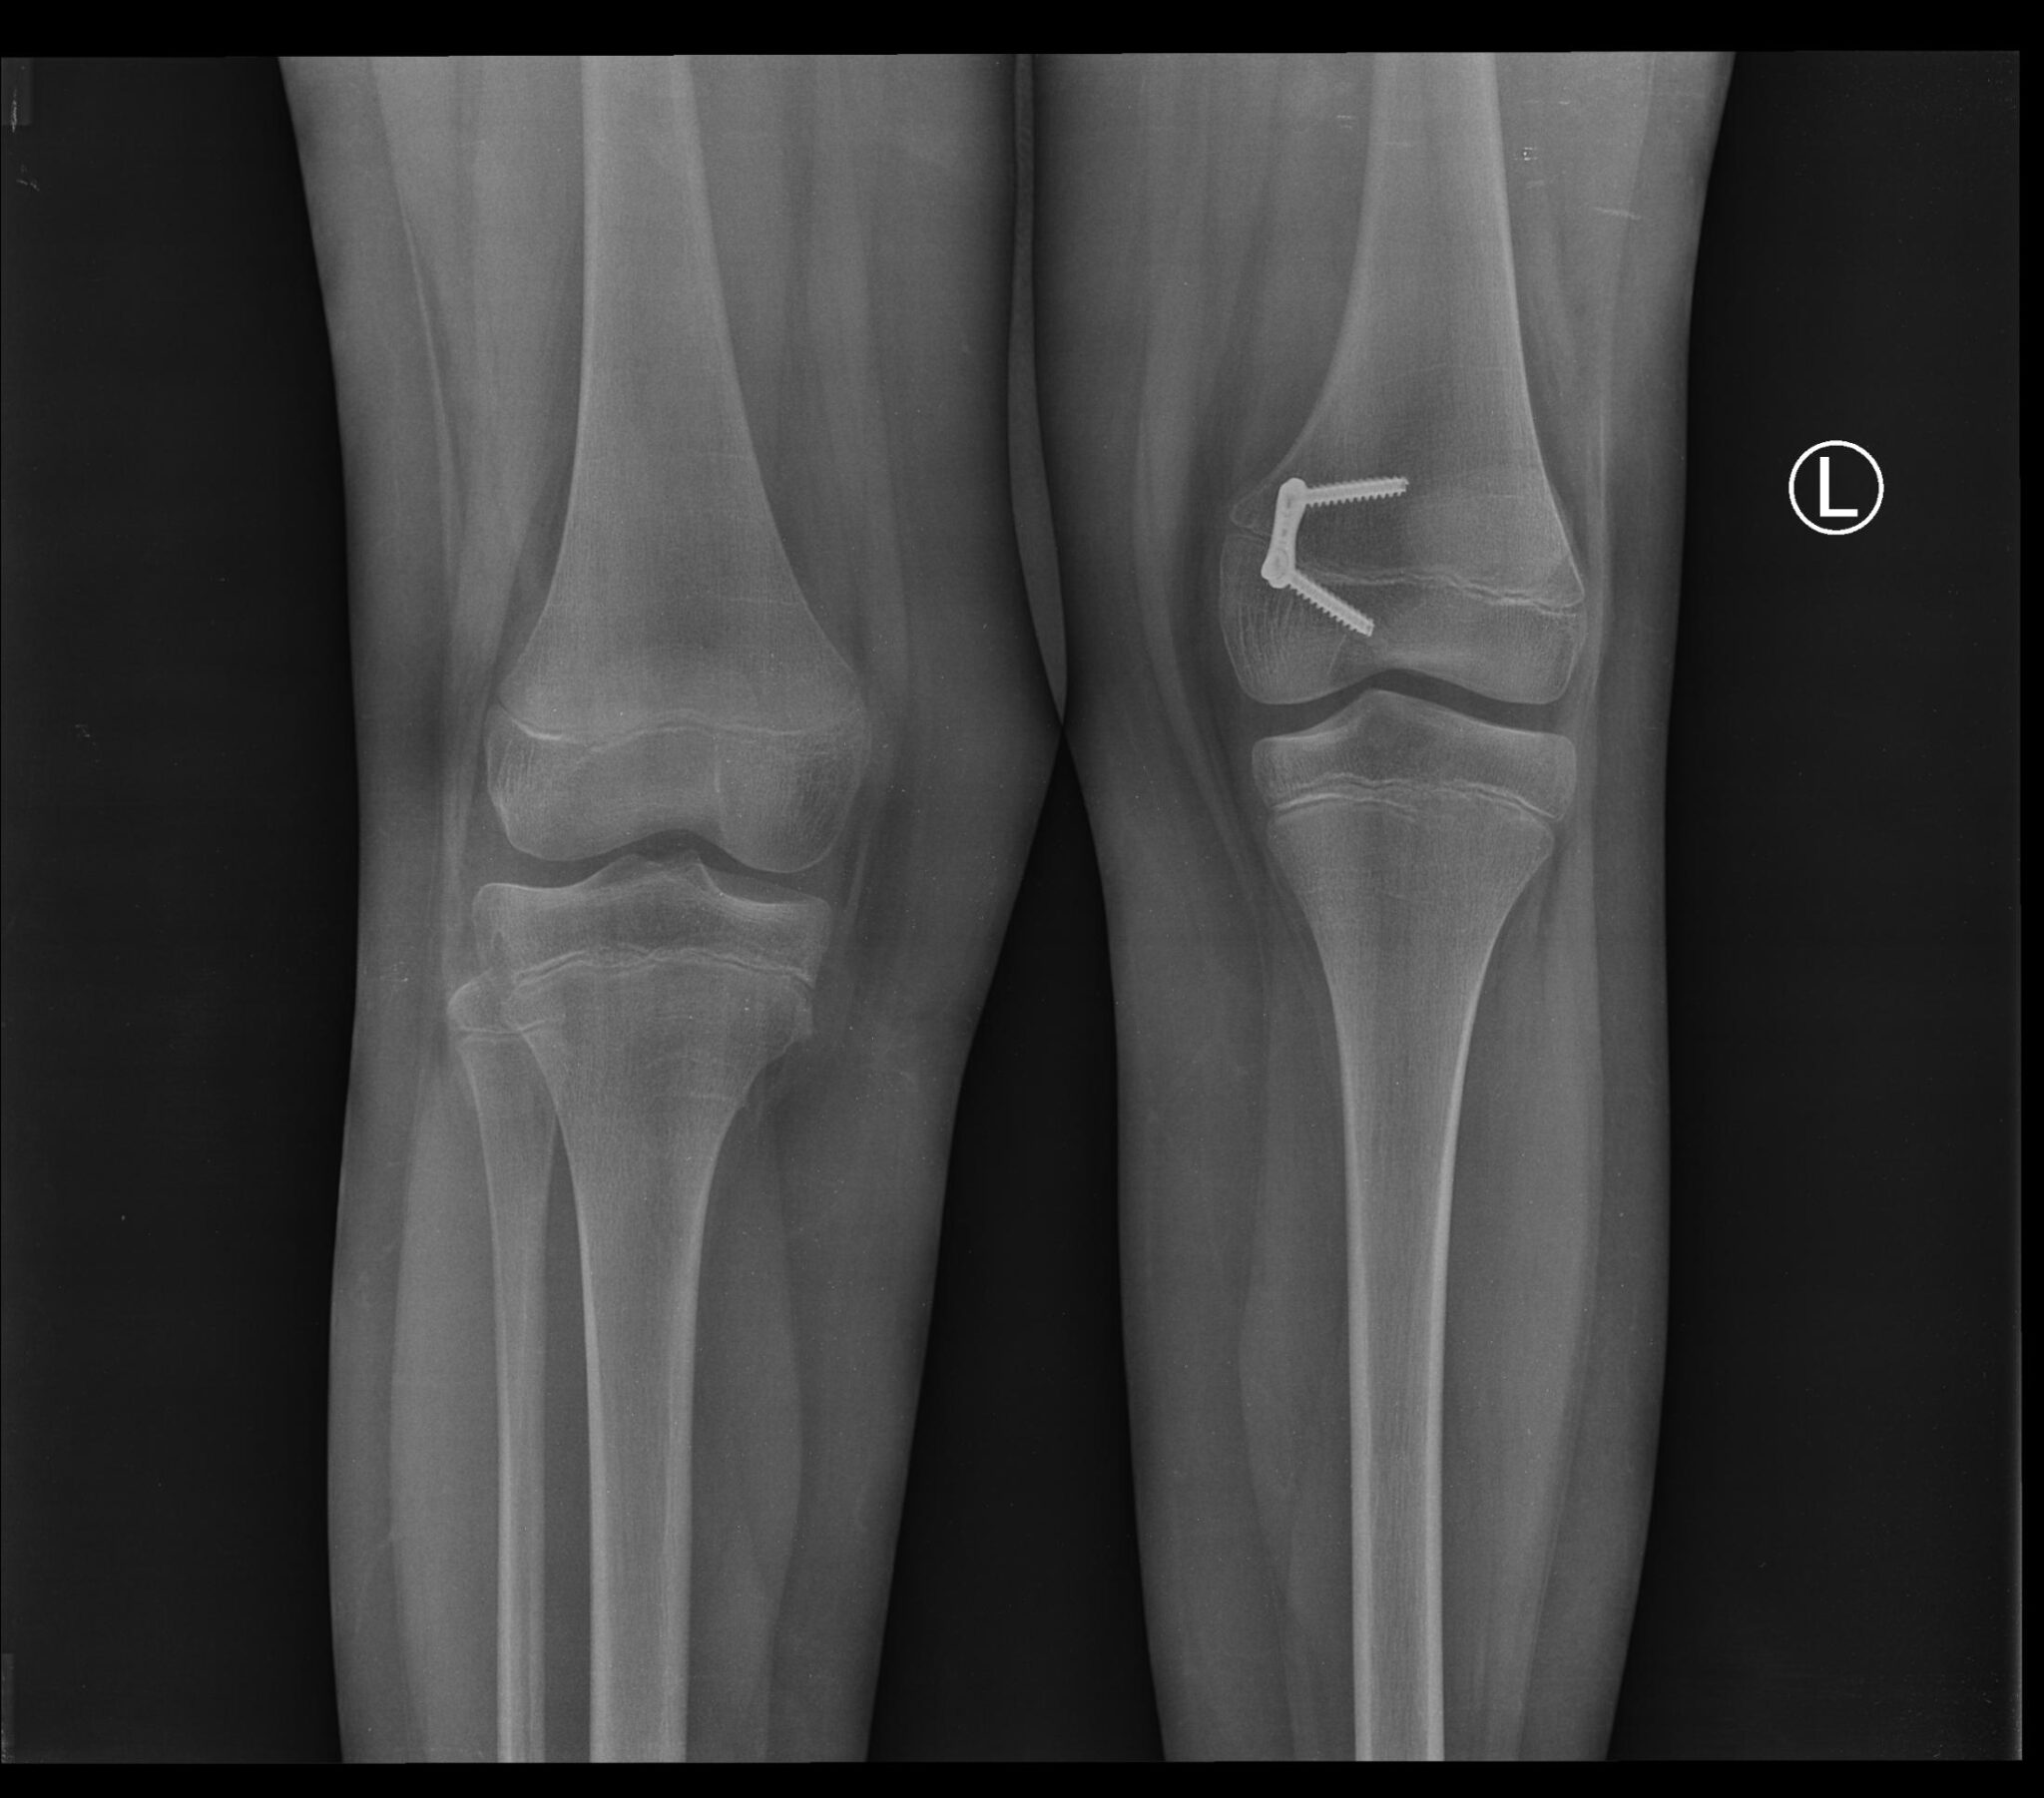

Nasz syn Mateusz urodził się 23 sierpnia 2009 roku jako zdrowy chłopiec. Po porodzie, ani wcześniej w czasie ciąży, nic nie wskazywało na późniejsze problemy zdrowotne. Jednak gdy synek zaczął stawać – robił to na paluszkach lewej nogi. Po wykonanych badaniach RTG okazało się, że Mateusz nie ma kości strzałkowej lewej, skrócenie piszczeli oraz kości udowej.

Po diagnozie szukaliśmy specjalistów, którzy pomogą nam w tej sytuacji. Trafiliśmy do szpitala w Łodzi, gdzie synek miał wykonane cztery operacje. Niestety nie poprawiły one stanu zdrowia dziecka, a wręcz uszkodziły lewą nogę. Przysporzyły jedynie dziecku cierpienia i naraziły na traumę.

Postanowiliśmy szukać pomocy u innych lekarzy. W 2018 roku trafiliśmy do Paley Institute w Warszawie, gdzie po badaniu okazało się, że Mateusz ma lewą nogę krótszą od prawej o 5 centymetrów. 25 kwietnia 2019 roku syn przeszedł pierwszą udaną operację, której koszt pokryliśmy ze środków własnych, a która miała na celu przygotowanie nogi syna do wydłużenia.